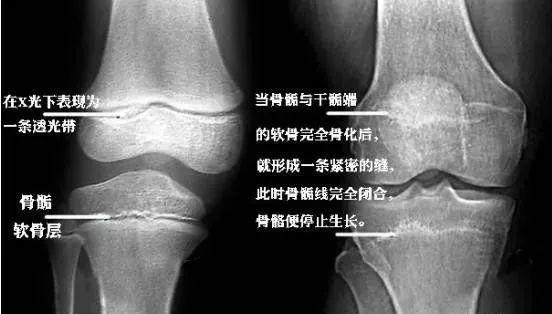

当骨骺线完全骨化不再生长时,骨骼也就停止生长, 人体的身高也就基本

骨骺线图片怎么看

骨骺线图解

骨骺线怎么看

骨骺线闭合图

骨骺线对照图

骨骺线闭合区别图

膝盖骨骺线闭合图

骨骺线基本闭合图片